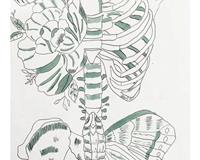

绘解生命奥秘 筑梦护理之路 ——丰润职教中心护理专业..

近期,丰润职教中心医学幼教部护理专业成功举办了一场别开生面的解剖创意绘画竞赛,该竞赛巧妙地将医学教.. |